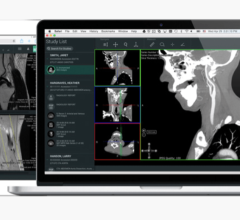

Barco has released a new version of their advanced visualization and analysis software, VOXAR 3D 6.1. The VOXAR suite incorporates clinical applications for CT cardiac analysis. Barco also introduced VOXAR 3D ENTERPRISE, which makes hospital-wide visualization accessible from the reading room and throughout the enterprise.

VOXAR 3D ENTERPRISE accelerates the speed at which image studies can be loaded, read and communicated. It also provides real-time interaction with VOXAR 3D’s visualization and analysis tools and clinical applications, VESSELMETRIX and CARDIAMETRIX.